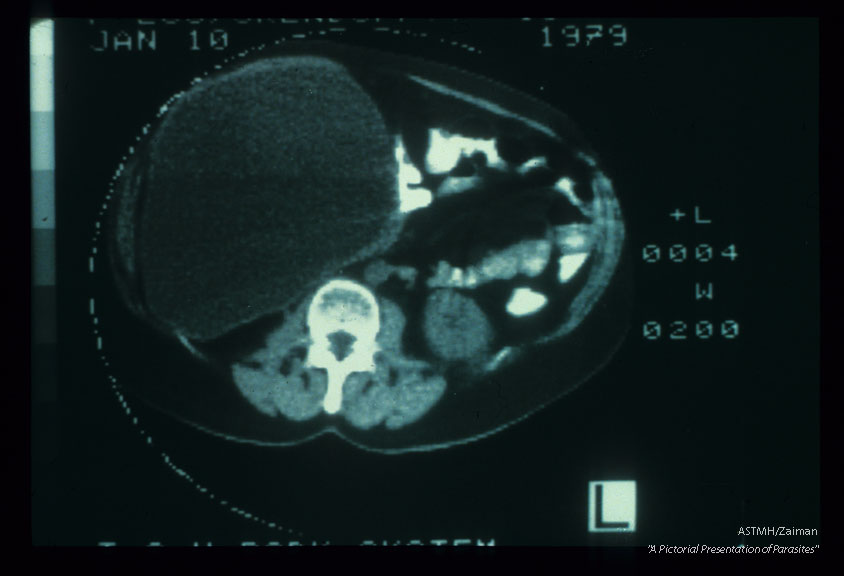

Intraperitoneal cyst. CT scan (1529) and surgical specimen.

Echinococcus granulosus

Description: Intraperitoneal cyst. CT scan (1529) and surgical specimen.